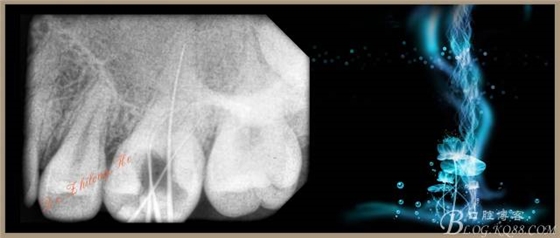

1、#26去暫封物,拔髓,手用#8、#10K銼探查根管。

2、手用#15K銼疏通根管+測(cè)量WL:P19.5mm,DB、MB、MB217mm。

3、C-SMART-1+根管馬達(dá)(COXO)+SC鎳鈦銼(SOCO)根管預(yù)備:

①?首先使用開口銼(08/30)敞開根管上段1/3~1/2之間,建立進(jìn)入根管的直線通道。

②?再用通道銼、成形銼逐級(jí)預(yù)備均至35#。(手法:輕微試壓,在到達(dá)WL后沿根管走向上下提拉4~5次)

?③預(yù)備過程反復(fù)用1%次氯酸鈉沖洗、超聲蕩洗和用EDTA潤(rùn)滑。

4、試主尖,側(cè)壓充填法根充,拍根充片,聚羧酸鋅暫封。